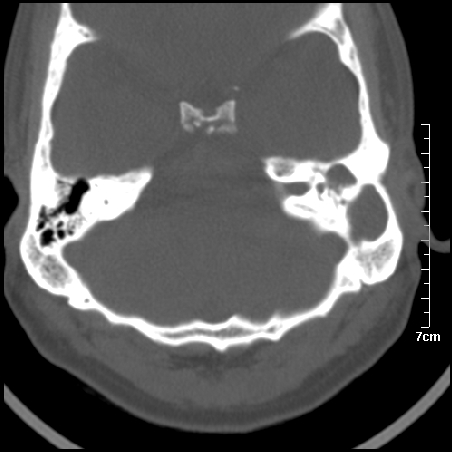

病例1

m/46y 头晕.耳鸣半月余 有乳突炎病史

左侧板障型乳突。